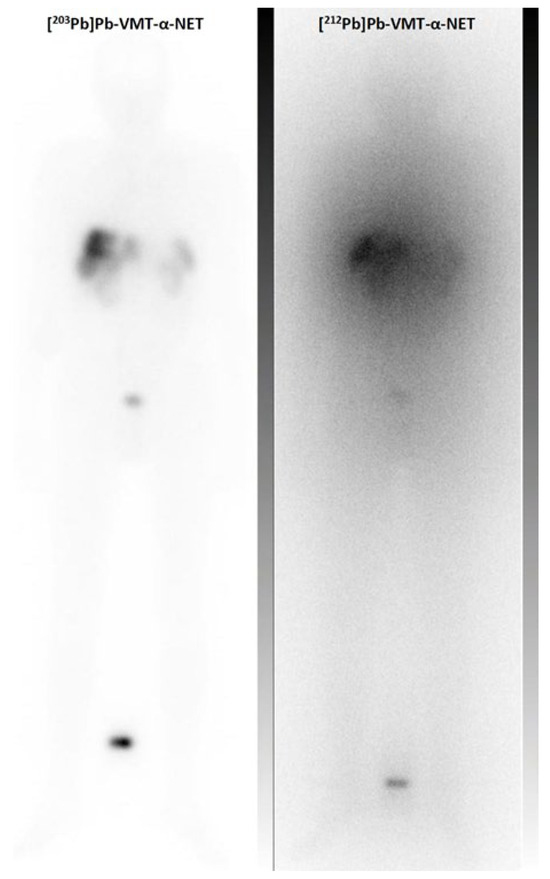

- Muller, D.; Herrmann, H.; Schultz, M.K.; Solbach, C.; Ettrich, T.; Prasad, V. 203Pb-VMT-alpha-NET Scintigraphy of a Patient With Neuroendocrine Tumor. Clin. Nucl. Med. 2023, 48, 54–55. [Google Scholar] [CrossRef] [PubMed]

- Michler, E.; Kastner, D.; Brogsitter, C.; Pretze, M.; Hartmann, H.; Freudenberg, R.; Schultz, M.K.; Kotzerke, J. First-in-human SPECT/CT imaging of [212Pb]Pb-VMT-alpha-NET in a patient with metastatic neuroendocrine tumor. Eur. J. Nucl. Med. Mol. Imaging 2023. [Google Scholar] [CrossRef] [PubMed]